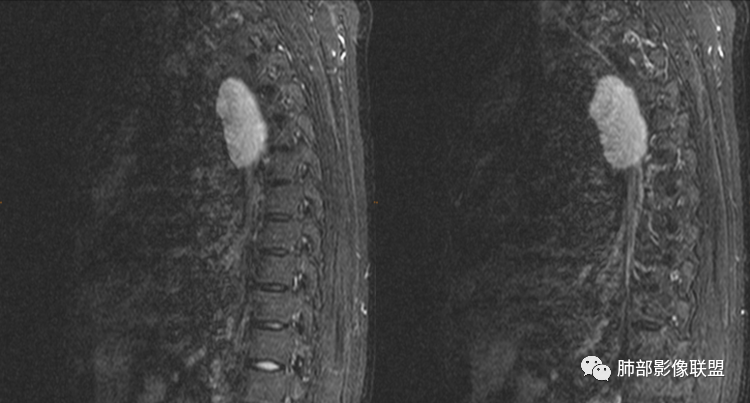

男性,43岁,体检发现后纵隔占位,边缘光整,CT示密度均匀,周围组织受压移位,无钙化囊变及脂肪组织,增强未见明显强化。MRI:T1示肿块信号较肌肉高,T2不均匀高信号。考虑为良性病变,第一是神经节细胞瘤,其次是支气管源性囊肿。

中年男性,无症状,后纵隔肿块,长径大矢状位于横径,质地偏软,塑形,等t1稍长t2,比较均质,增强轻微强化,与脊柱,主动脉,食管脂肪间隙存在,部分层面与脊柱相贴,骨质无改变,周围无肿大淋巴结,考虑神经源性肿瘤,节细胞神经瘤可能大,鉴别心包斜窦,淋巴瘤,淋巴管囊肿。

后纵隔囊性占位,密度均匀,与左主支气管分界不清,略受压,增强后强化不明显,核磁上看肿块局部突出,信号欠均匀,考虑良性,节细胞神经瘤可能大,支气管囊肿待排。

左后纵隔食管旁占位,边界清晰,增强目测未见明显强化,稍长T1稍长T2信号,信号尚均匀,病灶较软,和食管紧贴,定性良性,首先考虑前肠囊肿,以支气管囊肿可能性大,鉴别节细胞瘤。

定位,后纵隔囊性占位,边界清楚,内部密度均匀,张力高,囊壁均匀,周围结构受压,增强后无强化。MRI:长T2信号。考虑良性囊性病变,支气管囊肿、淋巴管囊肿。